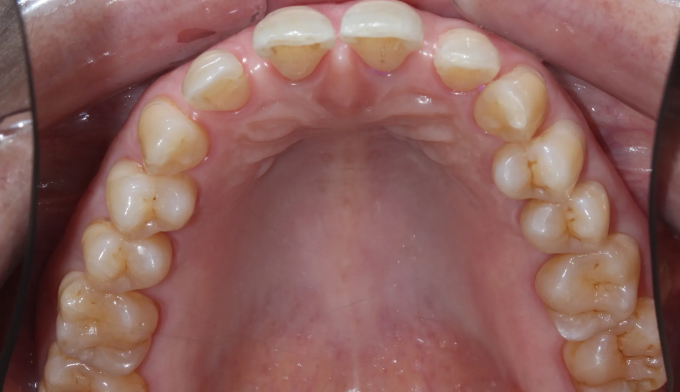

기존에 아래 앞니 사이 공간들에 레진이라는 치아색 나는 재료로 메워놓으셨던 분입니다. 나이가 들면서 잇몸이 약해지게되고 앞니가 점점 더 벌어질 수 있습니다.

타치과에서 다시 레진으로 공간을 없애려고 하였으나 더이상의 보철치료를 원하지 않으셔서, 기존에 존재하던 레진을 제거하면서 동시에 앞니 사이 공간을 교정치료를 이용해 닫아주기로 하였습니다.

기존에 앞니가 벌어지게 된 이유인 치주염을 치료하면서 동시에 앞니 공간을 교정을 통해 닫아줍니다.

총 교정기간은 9개월입니다.